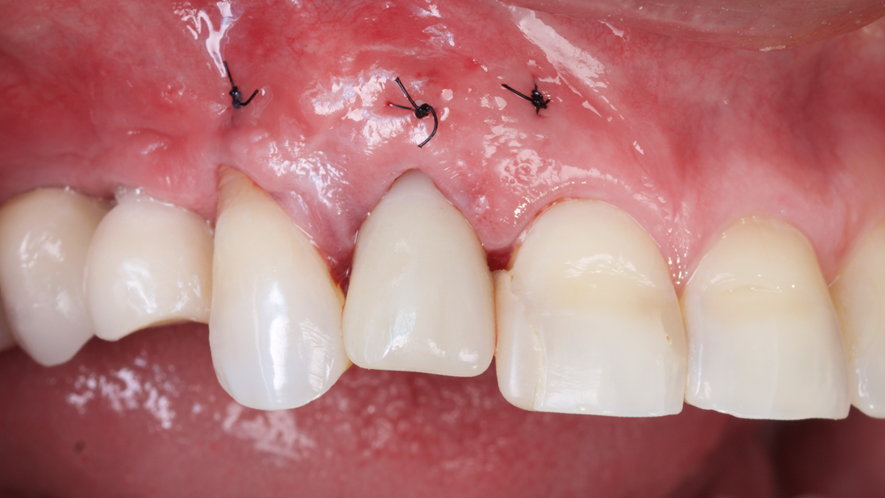

Este trabalho tem como objetivo relatar um caso clínico de exodontia minimamente invasiva de um incisivo lateral superior com fratura radicular, realizando implante imediato em alvéolo pós-extração, enxerto de tecido conjuntivo subepitelial e osso bovino liofilizado para preenchimento de GAP, prontamente à instalação de pilar reto e provisório imediato.